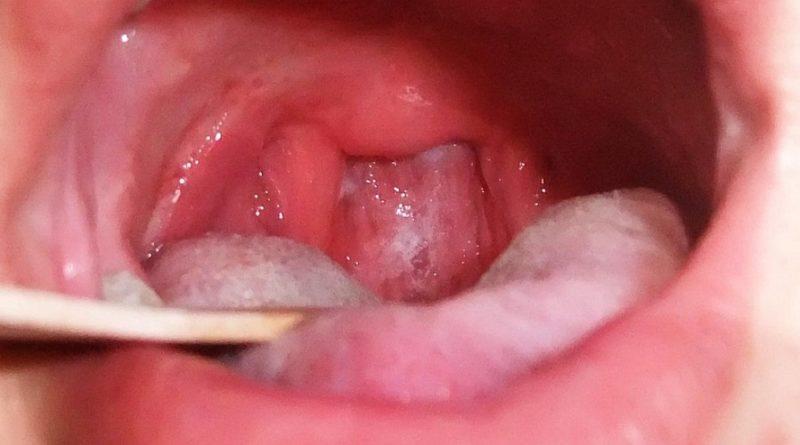

Как выглядит дифтерия

На представленных изображениях можно наблюдать, что дифтерия проявляется образованием плотного бело-серого налета на миндалинах, небных дужках и язычке. Кроме того, белый налет также присутствует на поверхности языка. Слизистая оболочка горла значительно воспалена, наблюдается выраженное покраснение и отечность.